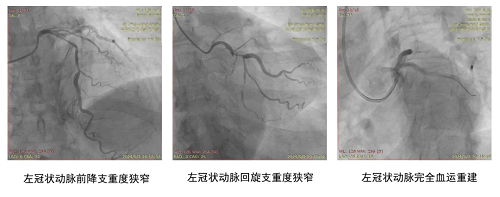

面对如此复杂且棘手的病情,吴阿姨家属慕名找到朝阳医院心内科赵林教授。赵林团队在入院后对患者进行个体化调整抗血小板药物和输血治疗,以降低便血带来的出血风险。经过冠脉造影检查,确认患者冠心病三支病变(累及LAD、LCX、RCA;LAD前降支,LCX回旋支,RCA右冠脉),且各支血管均存在严重狭窄。

针对患者的冠脉病变,赵林再次联合普外科、消化内科进行多学科MDT讨论,决定先干预冠脉,待心脏稳定1个月后再进行外科手术。赵林率团队为患者行PCI,直接干预LAD及LCX,过程顺利,手术成功。

赵林主任团队行介入治疗